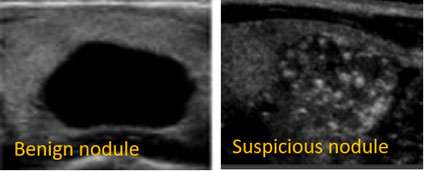

Thyroid nodules that are firm, fixed to adjacent structures such as the trachea, irregular in contour, growing rapidly, or associated with palpable cervical lymph nodes raise suspicion for malignancy. However, neither clinical examination nor isotope scanning alone can definitively differentiate between benign and malignant nodules. Notably, approximately 3% to 10% of thyroid carcinomas may appear as “hot” or “warm” nodules on imaging. Solitary nodules in children and men warrant particular caution, as they are more likely to be malignant.

A significant proportion of thyroid nodules, estimated to be around one-third, are primarily cystic in nature. These cystic nodules can sometimes be identified through palpation or ultrasound imaging (echograms). Some surgeons have begun treating cystic thyroid lesions with aspiration, which has shown promise in reducing the size of these nodules. Additionally, fine-needle aspiration (FNA) biopsy is increasingly being used as a diagnostic tool to determine whether a nodule is benign or malignant. While concerns exist regarding potential tumor spread and the possibility of false-negative results, these evolving techniques may ultimately transform the traditional indications for surgical intervention.